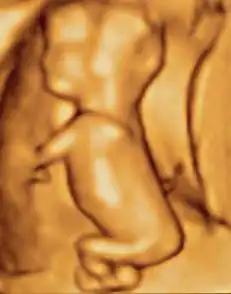

Fetus at 4+1⁄4 months -